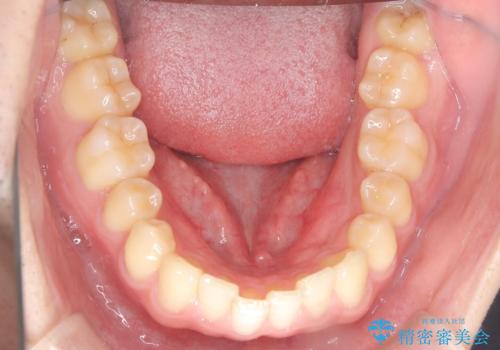

下顎の舌側傾斜気味の前歯も唇側へ歯軸傾斜させています。